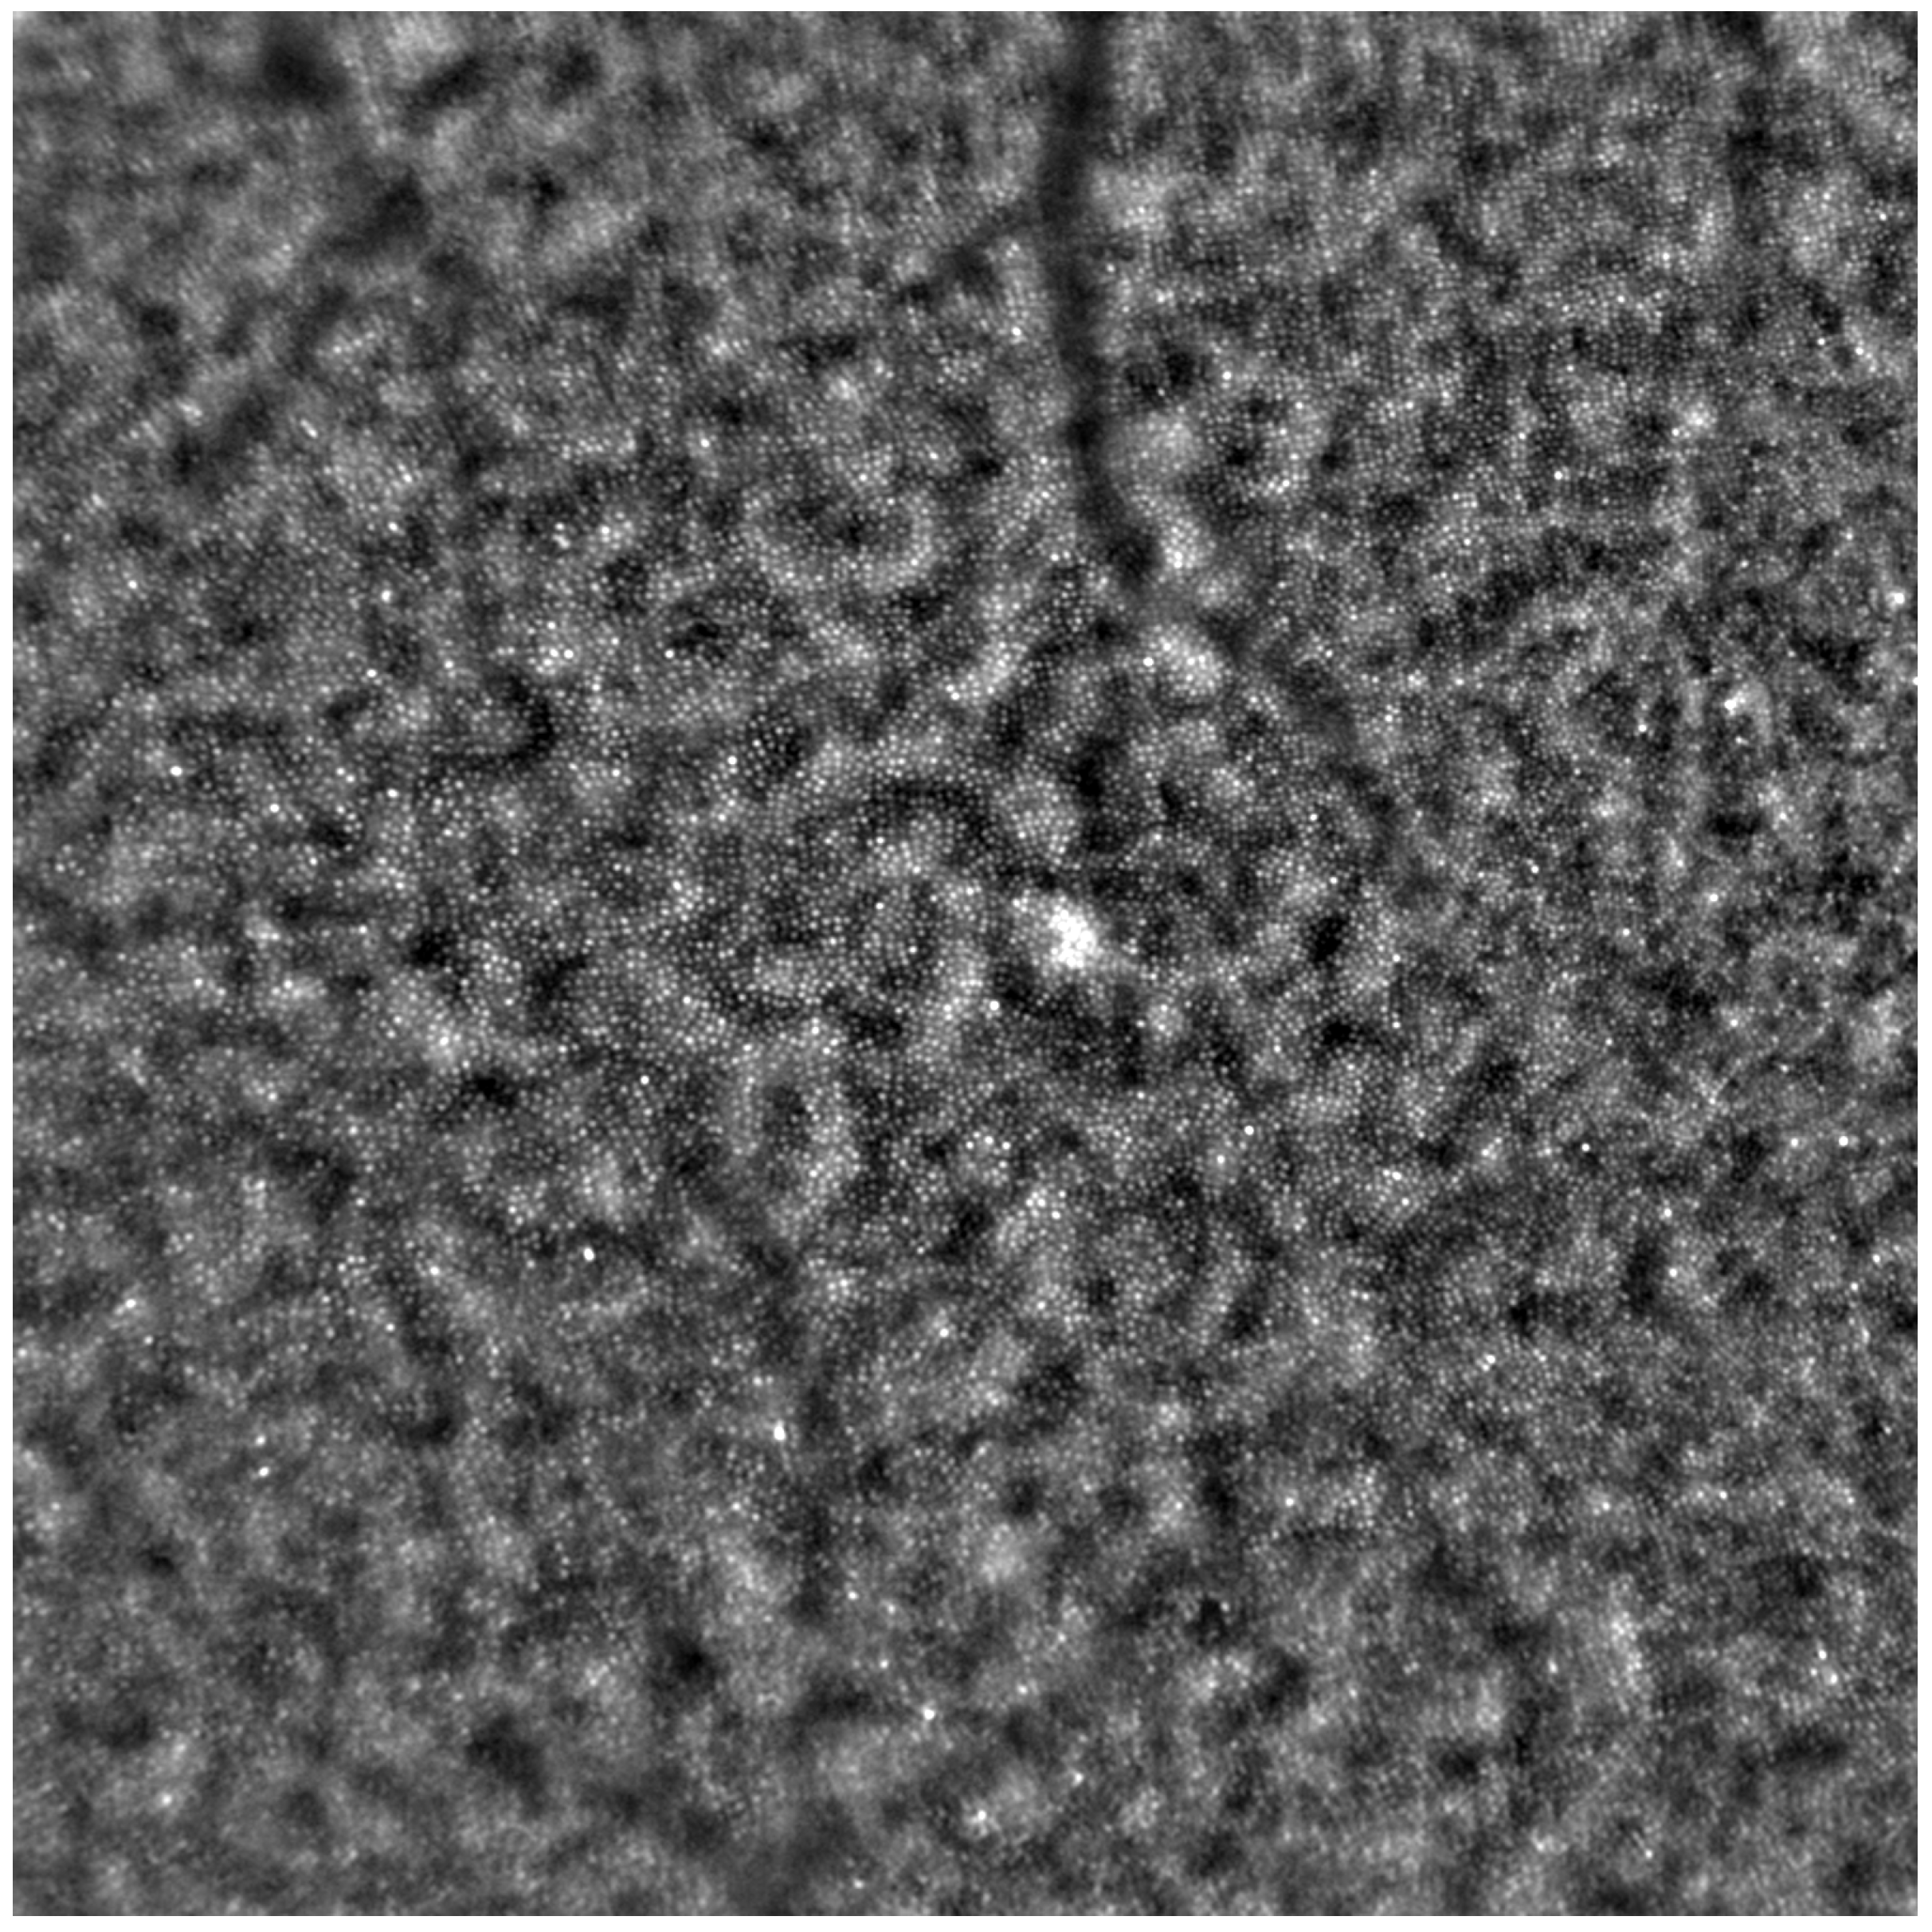

Adaptive optics retinal images depicting a healthy eye, CD, CRD, and STGD are presented in Figure 1, Figure 2, Figure 3 and Figure 4.

Figure 1 depicts the photoreceptor mosaic in a healthy eye. The image is taken paracentrally (2 ° superiorly) due to the limited ability of foveal image acquisition by Rtx™ [17]. By changing the focus point, the quality of an acquired image provides the assessment of photoreceptor parameters in parafoveal cones. The aberration and noise found in Figure 2, Figure 3 and Figure 4 are considered to be the result of poor fixation in eyes with impaired central vision in the course of macular disease. This issue has been addressed in our study. The assessment of factors predisposing for obtaining inadequate image quality was taken into consideration further in this article.

Figure 1. An adaptive optics image showing photoreceptors in a healthy eye (Rtx1™, Imagine Eyes, France). The photoreceptor mosaic appears intact (not disrupted) with individual photoreceptors visible as white and greyish spots.